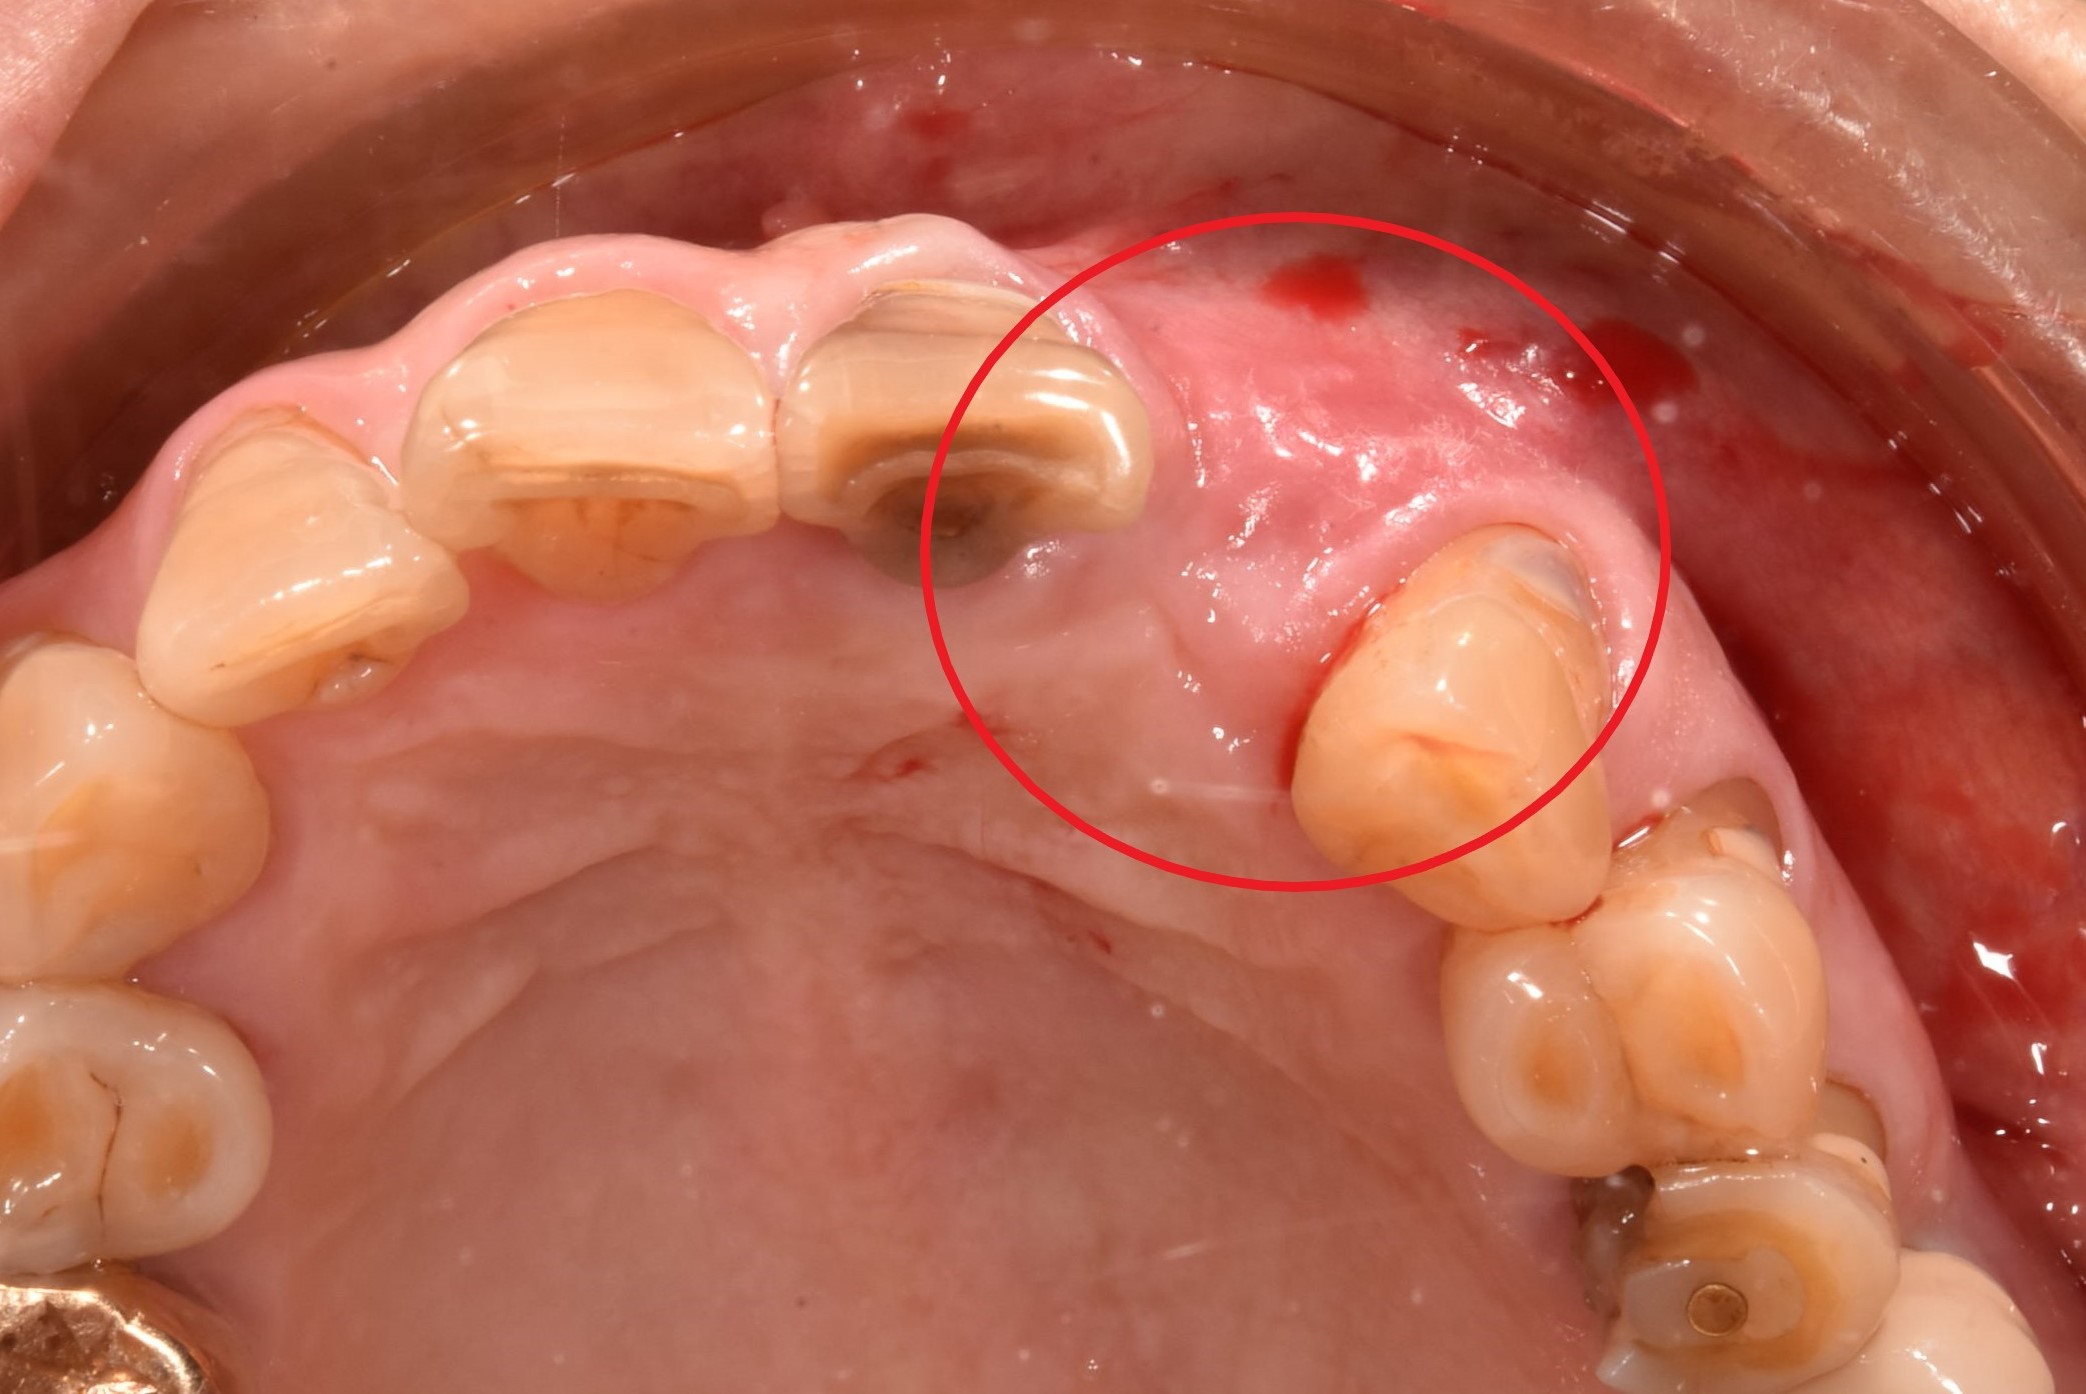

案例五

先把不好的牙根拔除,等待傷口癒合,進行補骨

翻瓣補骨的區域